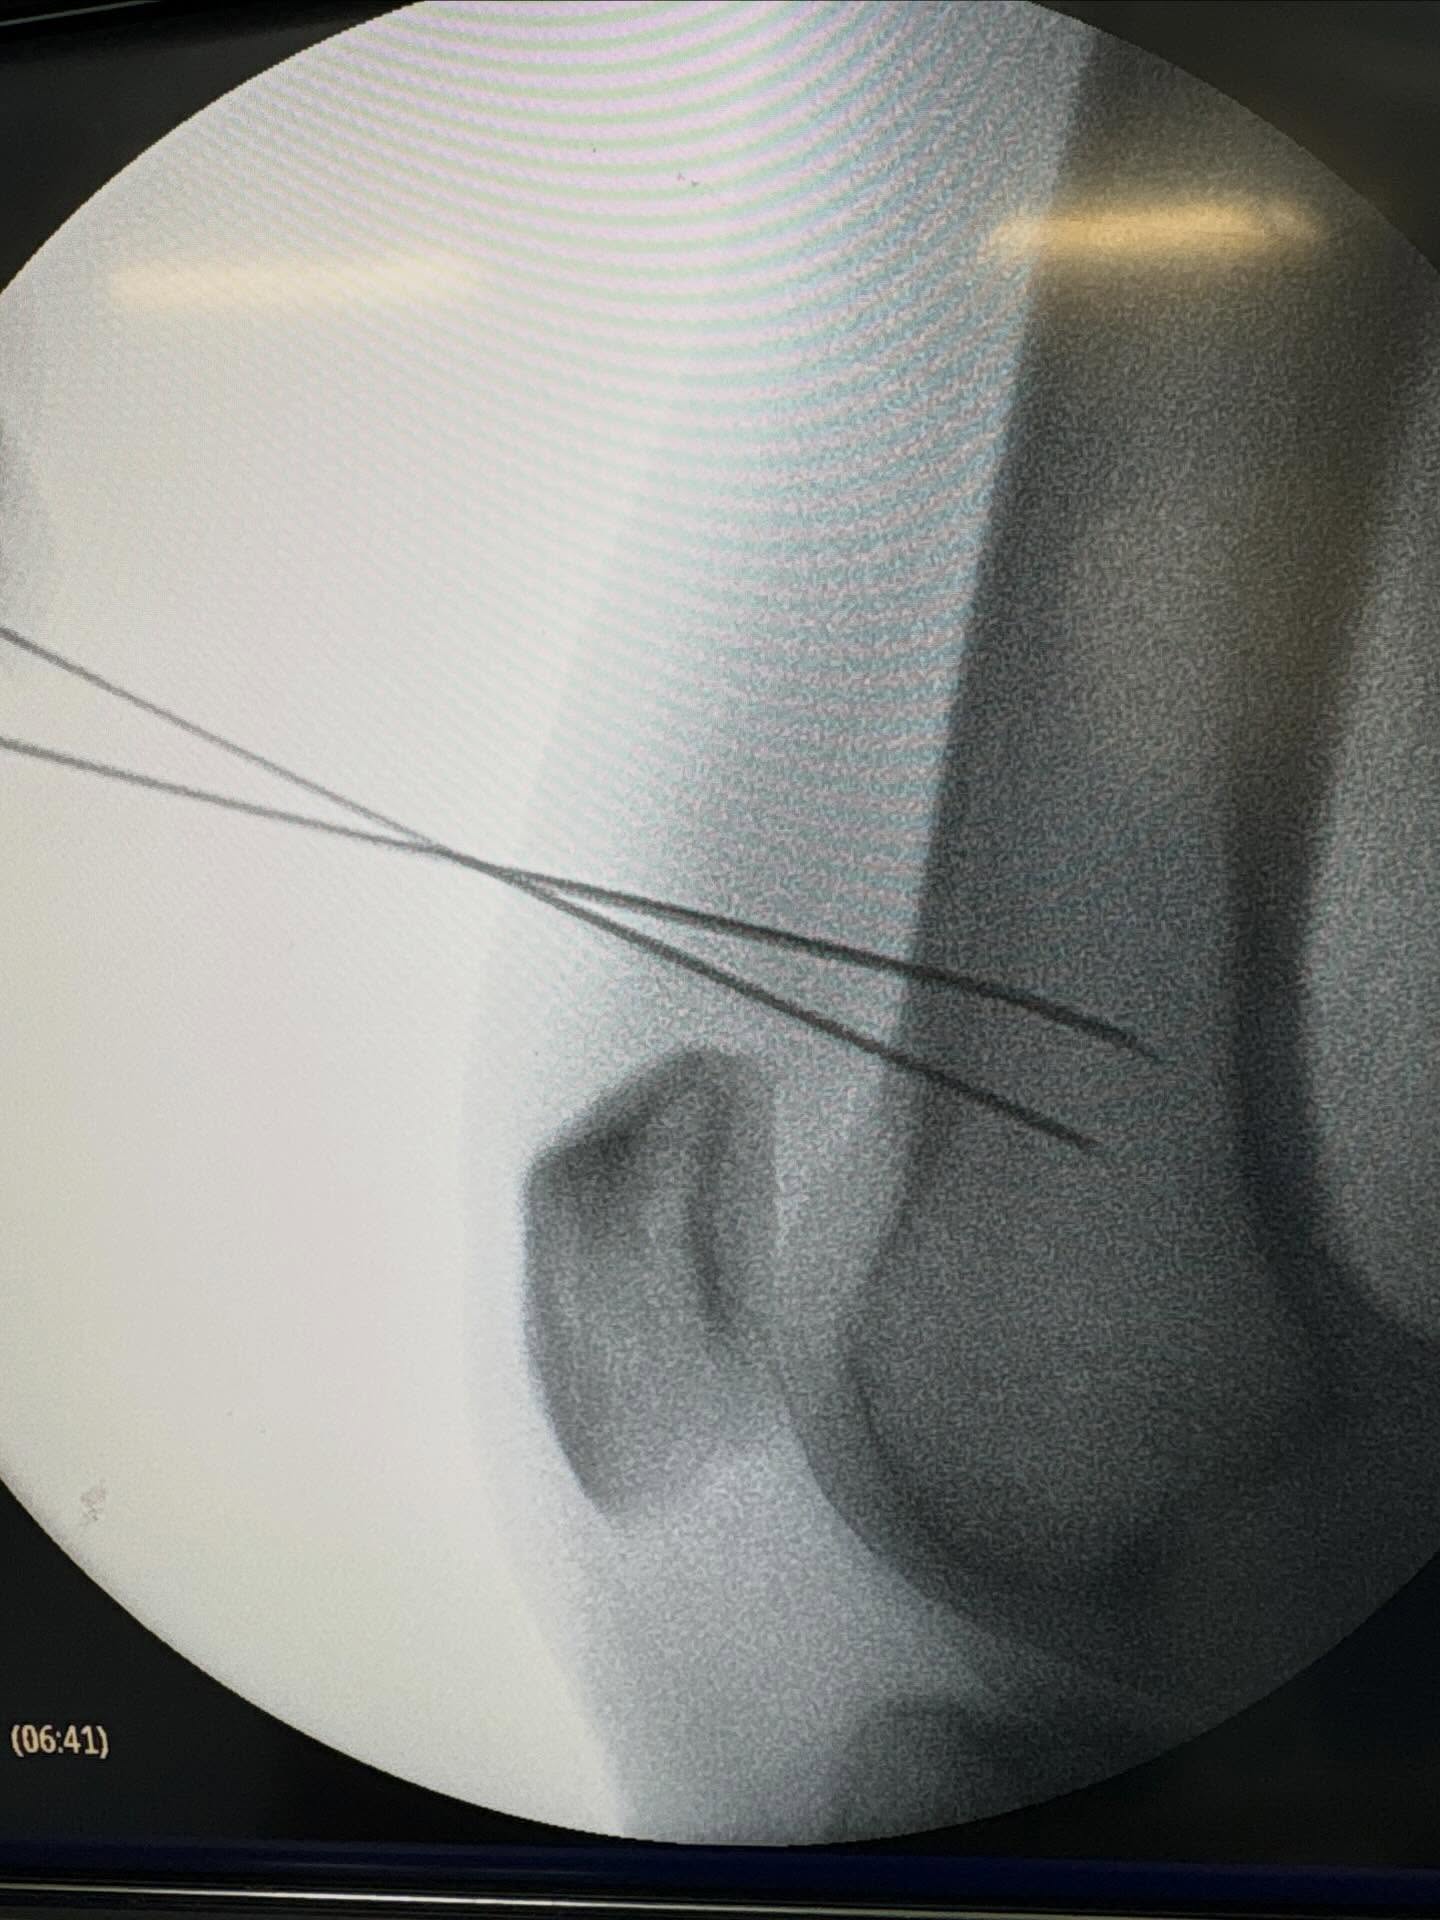

Traumatología y Ortopedia - Cirugía de Columna Vertebral

Soy el Dr. Saab Káram Magallanes Traumatólogo y ortopedista con alta especialidad en cirugía de columna vertebral de mínima invasión. Me especializo en en el diagnóstico y tratamiento de padecimientos del sistema musculoesquelético. Atiendo problemas musculares, articulares y de espalda, enfocado siempre en brindar una atención médica de calidad, personalizada y con un alto sentido de humanismo. Mi compromiso es acompañar a mis pacientes en la recuperación de su movilidad y en el alivio del dolor, ofreciendo mis conocimientos y experiencia médica. En cuanto a mi formación académica, me forme en algunas de las instituciones mas importantes del país. Soy egresado de la Universidad Autónoma de Nuevo León (UANL) como Médico Cirujano y Partero. Realice la especialidad en Traumatología y Ortopedia en el hospital ISSSTEP de Puebla, avalado por la Benemérita Universidad Autónoma de Puebla (BUAP). Posteriormente, realice un curso de alta especialidad en Cirugía de Columna Vertebral en el Swiss Hospital en Monterrey N.L. avalado por la Universidad de Monterrey (UDEM). Me encuentro acreditado ante el Consejo Mexicano de Ortopedia y Traumatología (CMOT), soy miembro activo de la Asociación Mexicana de Cirujanos de Columna (AMCICO), así como del Colegio Mexicano de Ortopedia Regenerativa, cuento con diversos cursos con respaldo académico por instituciones internacionales en el área de cirugía de columna vertebral de mínima invasión, me mantengo en constante actualización médica para ofrecer siempre la mejor atención a mis pacientes.